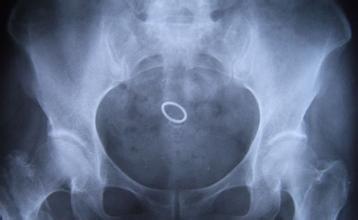

导读: 股骨头坏死是中老年人比较常见的骨关节病之一,可引起股骨头疼痛,从间断性疼痛会逐渐发展为持续性疼痛,然后在引起肌肉痉挛、关节活动受限等。如果不进行缓解呵护,甚至可能致残。

导读: 股骨头坏死了要怎么护理身体?如果生活习惯不好,如经常饮酒、剧烈运动等等,都可能引起许多的疾病,如股骨头坏死等。股骨头坏死会引起髋关节疼痛、活动受限等,会给患者朋友带来很大的影响。因此股骨头坏死后,要积